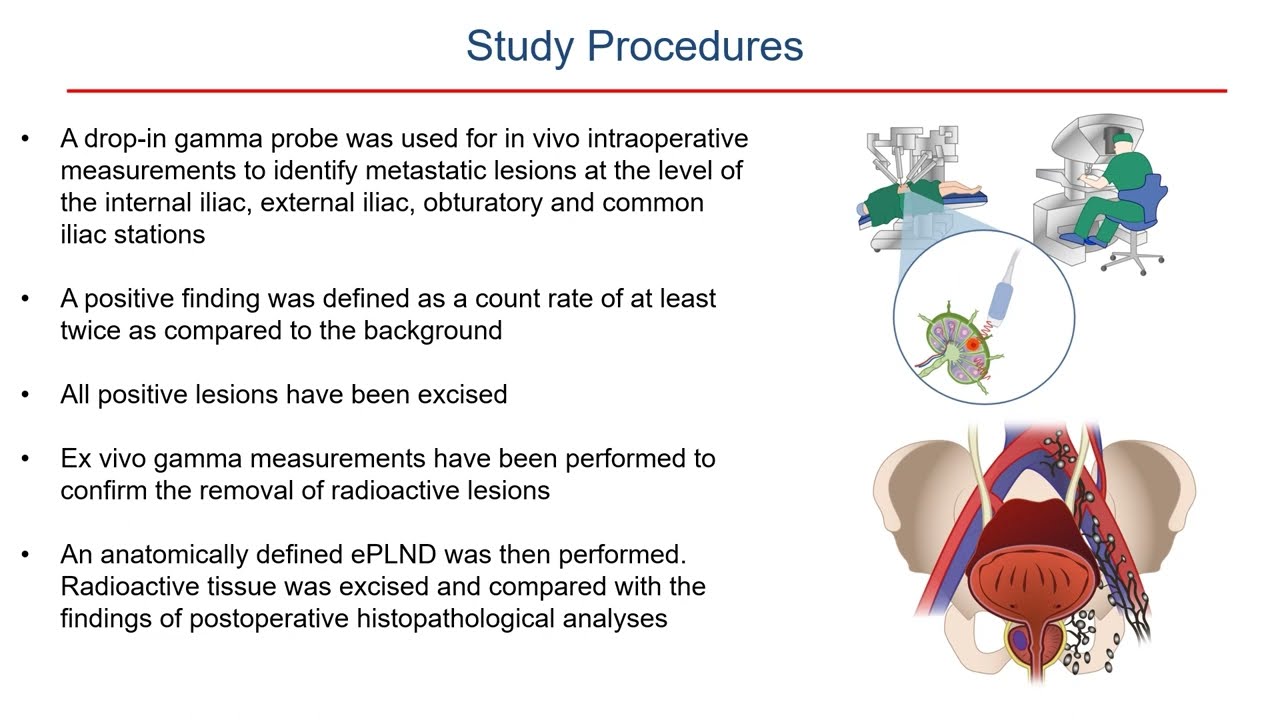

PSMA Radio Guided Surgery in Primary Prostate Cancer

Robot-assisted radioguided surgery using a DROP-IN gamma probe